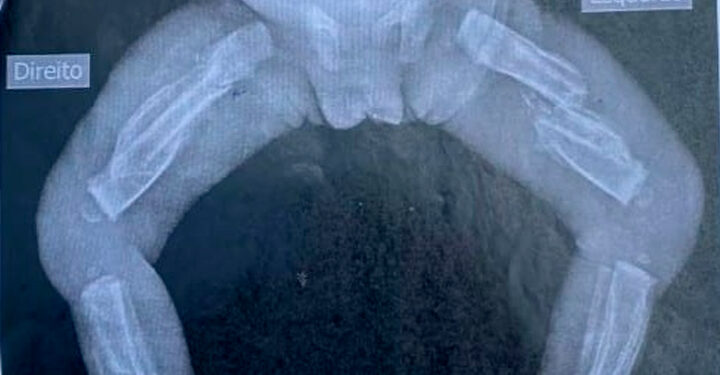

FLORIANÓPOLIS (SC) – Uma mulher de 23 anos foi presa no último domingo (13) suspeita de maltratar a própria filha, uma bebê de apenas 10 meses, em São João Batista, Florianópolis. O caso aconteceu na última sexta-feira (11) e a menina teve as duas pernas, costelas e braços quebrados, além de um roxo no olho e vários hematomas no corpo.

A criança foi atendida no Hospital Monsenhor José Loks, por volta das 19h, onde a equipe médica constatou que ela poderia ter sido arremessada no chão e pisoteada. O Conselho Tutelar foi acionado e descobriu que já existia uma outra denúncia, há aproximadamente 20 dias, sobre a mesma bebê.